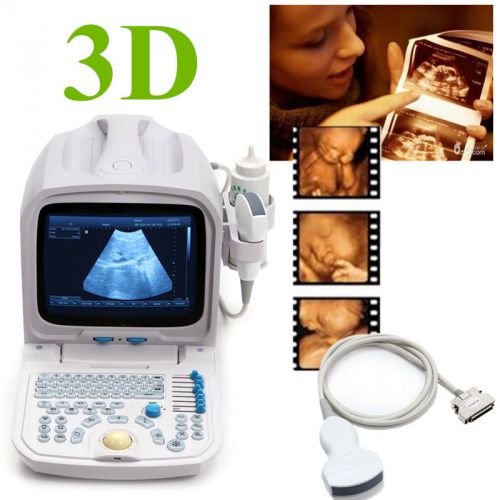

3D PC Plateform Based Full Digital Portable Ultrasound Scanner+3.5mhz convex pro

Internal 3D 3.5mhz convex probe Portable Ultrasound Scanner machine warranty